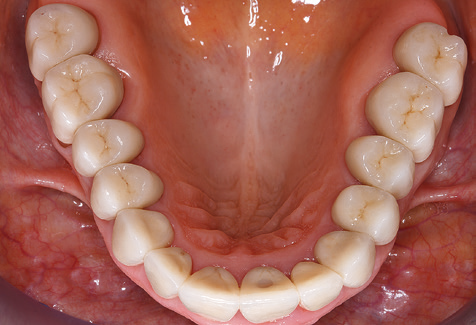

Aufgrund der bestehenden parodontalen Vorerkrankung erfolgte die unterstützende Parodontaltherapie (UPT) in den ersten Jahren in einem Drei­Monats­Intervall. Dabei zeigte die Patientin eine hohe Motivation und gute Compliance. Bei den jährlich erhobenen Sondierungsbefunden zeigten sich stabile parodontale Verhältnisse mit einem BOP­Index unter fünf Prozent. Aufgrund der stabilen parodontalen Situation und der guten Mitarbeit der Patientin wurde ab dem sechsten Jahr der prothetischen Funktionsphase das Recallintervall auf halbjährlich um­gestellt. Auch mit diesem veränderten Recallintervall zeigten sich bei der jeweils jährlichen Aufnahme des Parodontalstatus stabile parodontale Verhältnisse, ohne Zunahme der Sondierungstiefen und einem BOP­Index unter fünf Prozent (Abb. 2a und b).

Abb. 9: Die Politur der zugänglichen Implantat­ und Zahnoberflächen erfolgt mit Polierkelchen und geeigneten Polierpasten. – Abb. 10: Die Reinstruktion zur Anwendung geeigneter Hilfsmittel bei der häuslichen Mundhygiene sollte ebenfalls Bestandteil der UPT sein. – Abb. 11a und b: Klinische Situation zwölf Jahre nach Insertion der prothetischen Versorgung. In diesem Zeitraum kam es lediglich zu einer Verblendkeramikfraktur am Zahn 47 und der Notwendigkeit einer endodontischen Behandlung am Zahn 12. Sämtliche Restaurationen sind noch in Funktion.

Für den klinischen Langzeiterfolg des parodontal kompromittierten Patienten ist die standardisierte und regelmäßige risikoadaptierte Betreuung im Rahmen der UPT der zentrale Baustein des Behandlungserfolgs. Dies gilt in besonderer Weise für Patienten, die nach erfolgreich abgeschlossener parodontaler Sanierung mit Implantaten versorgt wurden (Abb. 11a und b).